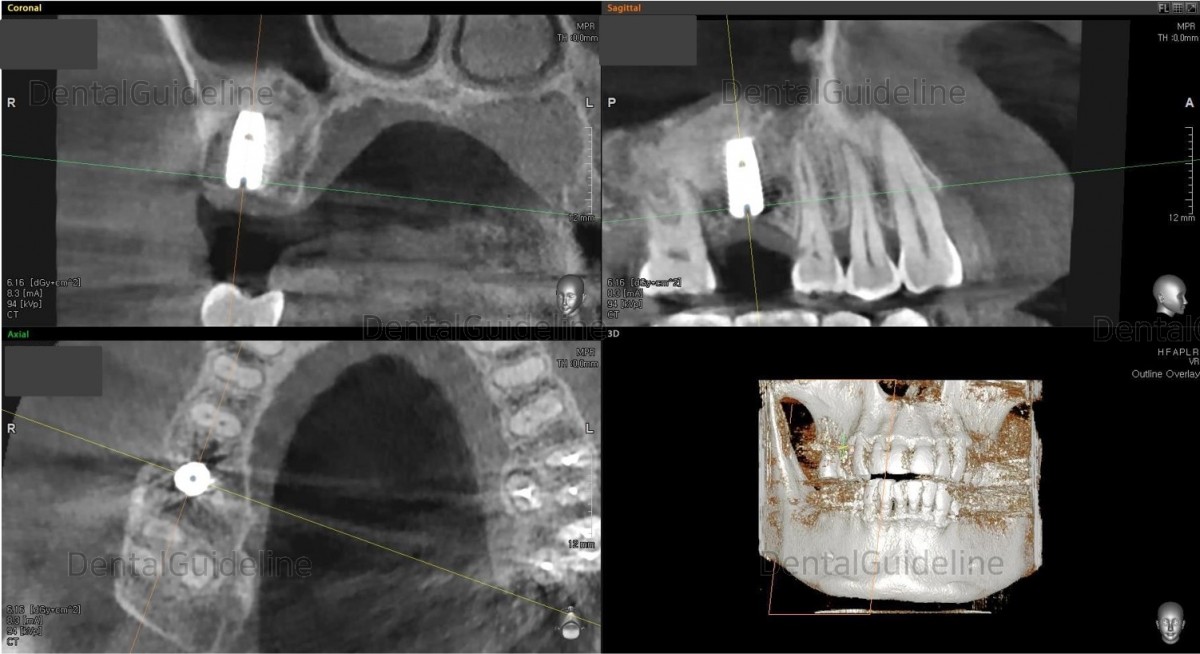

1. CBCT scan. Before maxillary sinus graft. ![]()